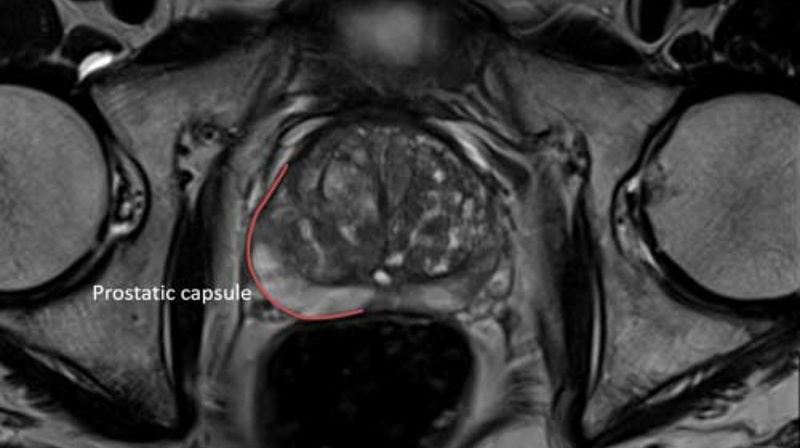

MRI scan

Learn how MRI scans can help to diagnose prostate cancer, the advantages and disadvantages of the scan, and what the results mean.